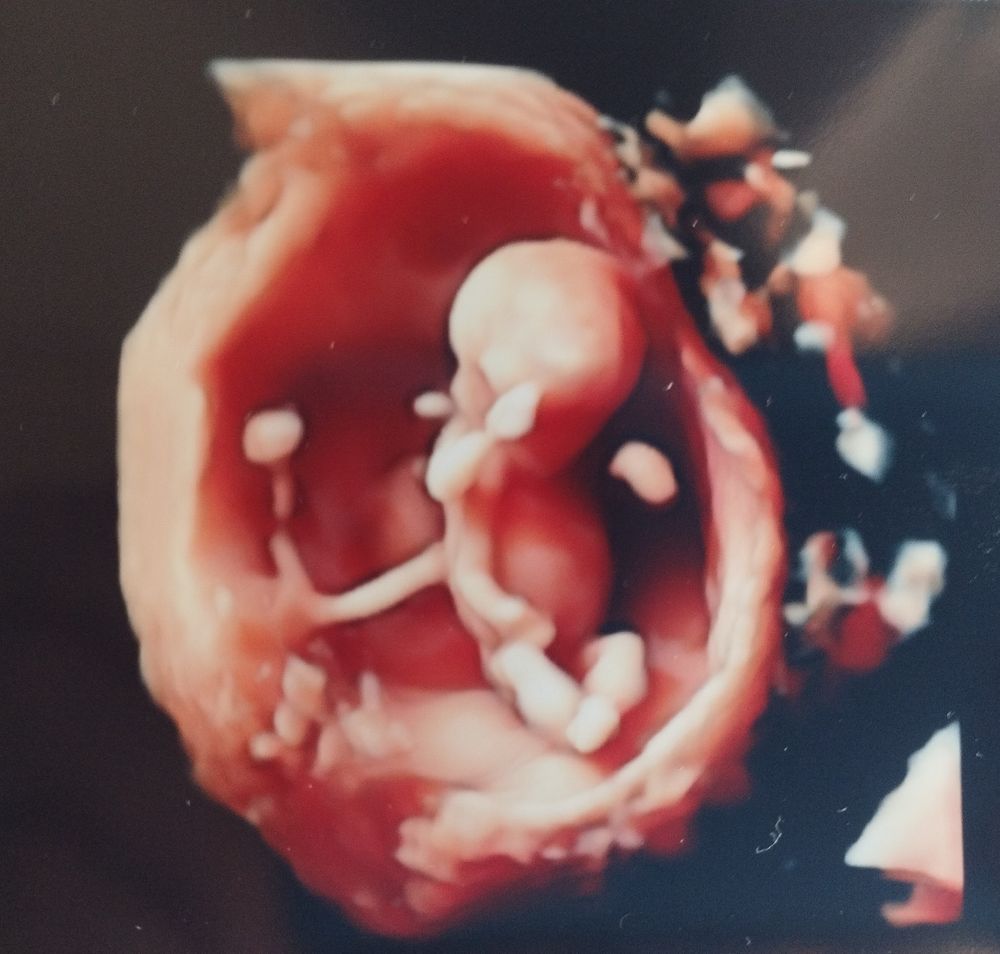

Боже какая прелесть 😍😍😍

Поздравляю! Цветная фоточка 👍

Боже, ну какое же это чудо и счастье😍 Я вас искренне поздравляю, что с малышом все хорошо❤️